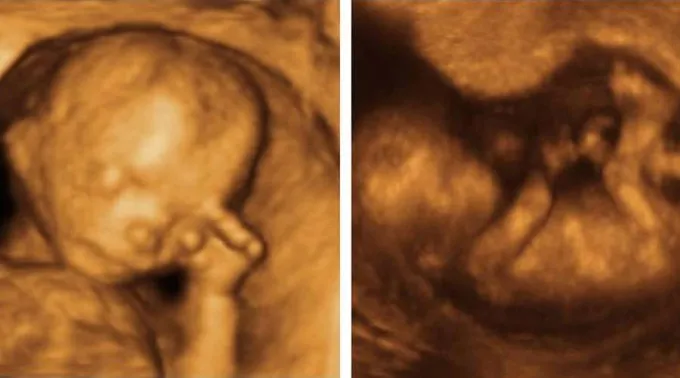

Um projeto de lei apresentado recentemente em Ohio (Estados Unidos) propõe ensinar nas escolas públicas como é o desenvolvimento fetal de um bebê em gestação.

O projeto HB90, conhecido como "Humanidade do Nascituro", permitiria que a secretaria de educação e o departamento de saúde do estado de Ohio gerem um currículo escolar que "forneça informações precisas e cientificamente verificáveis sobre características anatômicas e fisiológicas do nascituro” durante a gravidez.

O projeto foi apresentado pelo republicano Niraj Antani, que disse ao jornal ‘Columbus Dispatch’ que, "quando se aprende que o coração de um bebê começa a bater com seis ou oito semanas, que as unhas se formam com dez semanas e que com 20 semanas já sente dor, tudo isso, sem dúvida, ajudará a criar uma cultura de vida”.